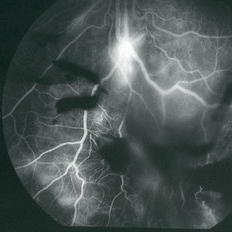

Mid-phase fluorescein angiogram frame of the left eye of a 23-year-old Vietnamese female with Eales Disease showing multiple areas of NVE and areas of capillary loss and nonperfusion OS.

Imaging device: Topcon VT-50

Condition/keywords: Eales disease, FA mid phase, fluorescein angiogram (FA), neovascularization elsewhere (NVE)